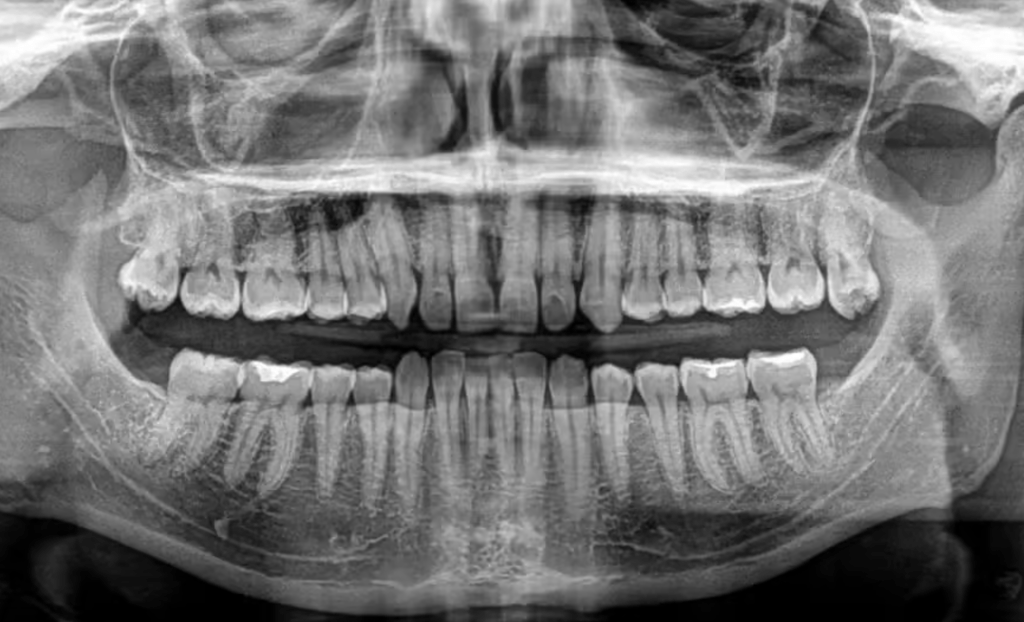

Zdjęcie pantomograficzne, znane również jako RTG panoramiczne, to jedno z najczęściej wykonywanych badań stomatologicznych. Umożliwia uzyskanie pełnego obrazu wszystkich zębów, kości szczęki i żuchwy oraz stawów skroniowo-żuchwowych w jednym ujęciu.

W naszej pracowni RTG stomatologicznego w Gdyni wykonujemy zdjęcia panoramiczne, które stanowią podstawę diagnostyki przed rozpoczęciem leczenia zachowawczego, chirurgicznego czy ortodontycznego. Badanie pozwala ocenić ogólny stan uzębienia, wykryć próchnicę, stany zapalne, torbiele czy inne nieprawidłowości w obrębie jamy ustnej.